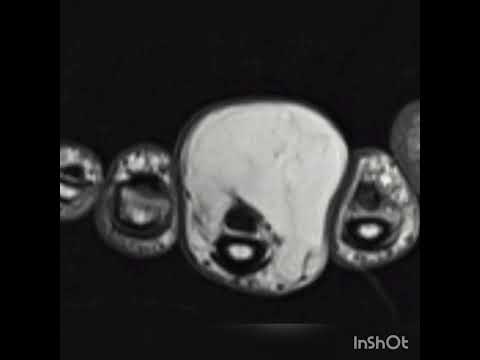

Kemik tümörlerinin tanısında basit röntgenler çok önem taşır ve doğru şekilde değerlendirildiğinde yeterli olabilir. Ancak kötü huylu olabileceği düşünülen ya da yumuşak doku tümörlerinde mutlaka MR çekilmelidir. MR kontrastlı olmalı ve yeterli kalitede olacak şekilde çekilmelidir. Aksi halde hasta tekrar MR çektirmek zorundadır. Kemik tümörlerinde zaman zaman bilgisayarlı tomografiden de yararlanılır. Ayrıca kemik taraması isteniyorsa, ya da tümörün diğer kemiklere yayılıp yayılmadığının anlaşılabilmesi için kemik sintigrafisi de önem taşır. PET ise son derece özel bir görüntüleme yöntemi olup henüz tanı almamış hastalar için yeri yoktur.